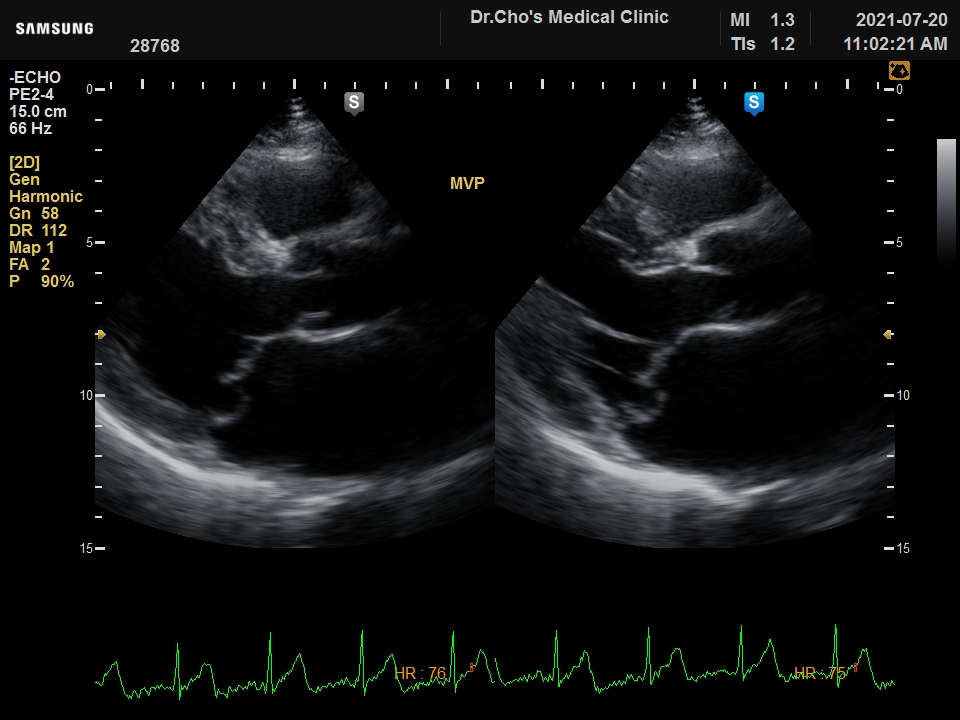

ÃÊÀ½ÆÄ°¶·¯¸®

½Â¸ðÆÇ Å»...

½É³¶ »ïÃâ